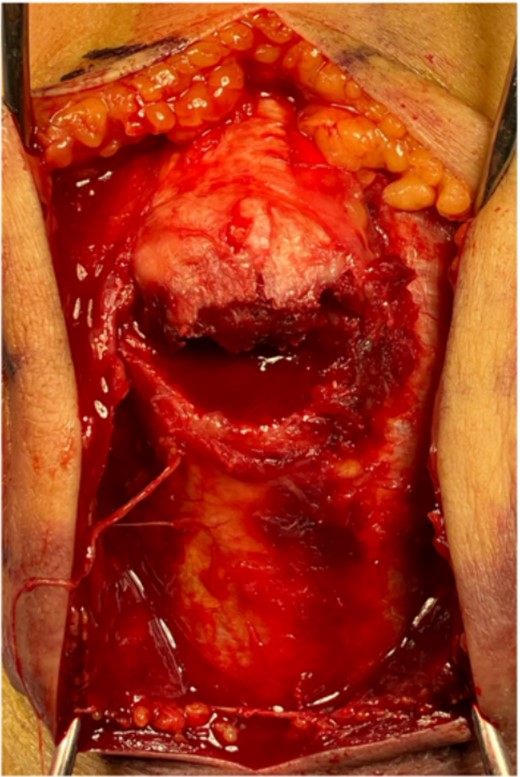

The surgery was performed in the left lateral recumbent position. An incision was made in the posterior midline over the right olecranon. Triceps brachii tendon rupture was not observed (Fig. 2). The fracture fragment was inverted, and two 1.4-mm JuggerKnot® All-Suture Anchors (Zimmer Biomet, USA) were inserted into the ulna proximal to the fracture site without perforation into the elbow joint. Subsequently, sutures were threaded through the triceps brachii muscle; the dislocated bone fragment was pulled together with the triceps brachii muscle. Despite maintaining the elbow at a 30° flexion position, two Quattro® Link Knotless anchors (Zimmer Biomet, USA) were inserted into the ulna distal to the fracture site to reduce and fix the fragment using the suture bridge procedure (Fig. 3). However, upon flexing the elbow joint to 90°, the bone fragment was displaced and anchors were loose. Therefore, we opted to use the McLaughlin cerclage technique, utilizing a 2.3-mm BroadBand® Tape (Zimmer Biomet, USA) passing through a predrilled hole perpendicular to the ulnar shaft. The suture was crossed over the posterior aspect of the ulna and tightened in a figure-of-eight manner through the triceps brachii tendon (Fig. 4). This procedure resulted in no dislocation of the fracture site, even when the elbow joint was flexed to 130°.

(A) Addition of McLaughlin cerclage using BroadBand® Tape. (B) A schematic of the surgical field is shown. The artificial ligament is fastened in a figure-of-eight configuration.